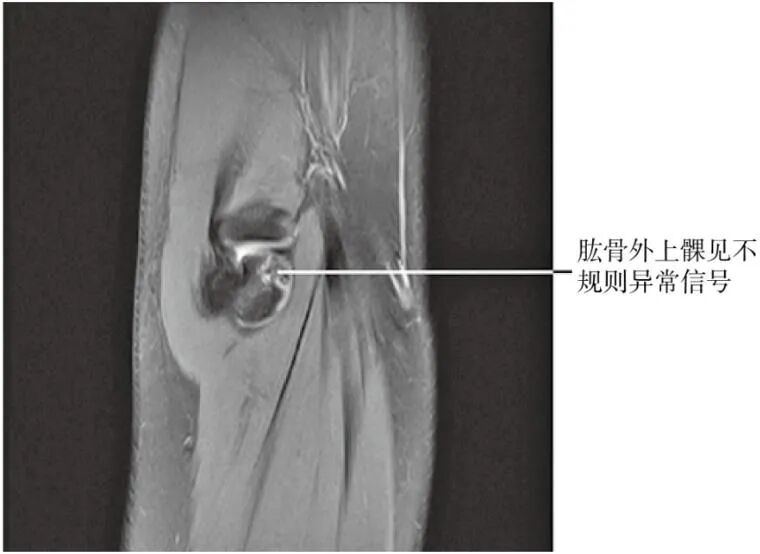

【MRI检查】

可见异常信号。(图2)

图2 肱骨外上髁MRI片